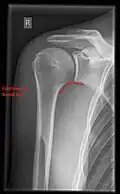

Imaging

Imaging of the shoulder includes ultrasound, X-ray and MRI, and is guided by the suspected diagnosis and presenting symptoms.

Conventional x-rays and ultrasonography are the primary tools used to confirm a diagnosis of injuries sustained to the rotator cuff. For extended clinical questions, imaging through Magnetic Resonance with or without intraarticular contrast agent is indicated.

Hodler et al. recommend starting scanning with conventional x-rays taken from at least two planes, since this method gives a wide first impression and even has the chance of exposing any frequent shoulder pathologies, i.e., decompensated rotator cuff tears, tendinitis calcarea, dislocations, fractures, usures, and/or osteophytes. Furthermore, x-rays are required for the planning of an optimal CT or MR image.[25]

X-ray

Projectional radiography views of the shoulder include: